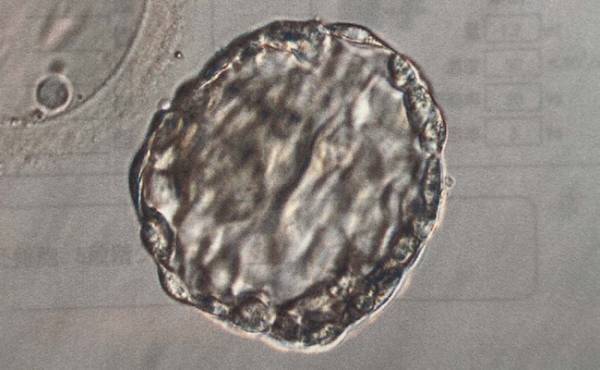

治療を始めて4年半が経過しましたが、体外受精で2人目を妊娠することができました。

長男とは5歳差になりましたが、やっと授かった命を夫も長男も大喜びしてくれました。